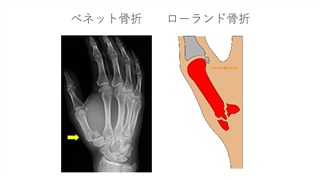

母指基部骨折は、大菱形骨中手骨関節の脱臼を伴うことがよくあります。これらの損傷は、母指中手骨が屈曲した状態で軸方向の荷重を受けることで発生します。一般的な病名として、「ベネット骨折」と「ローランド骨折」の2つがよく知られています。ベネット骨折は、母指中手骨基部の関節内骨折亜脱臼です。ベネット骨片は掌側靭帯によって固定されていますが、中手骨の残りの部分は長母指外転筋と母指内転筋の牽引により近位、背側、および橈側へ転位します。ベネット骨折の治療は、通常、関節適合性の回復を目的として、徒手整復と経皮的ピン固定を行います。徒手整復で整復できない場合は、観血的整復が必要です。メタアナリシスによると、手術的治療は非手術的治療と比較して疼痛緩和効果は大きいものの、合併症リスクは高いことが示されています。ローランド骨折は、母指中手骨基部のT字型またはY字型の関節内パターンを示す骨折です。これは、母指中手骨基部の粉砕性関節内骨折を総称して用いることが多いです。治療の適応と手技はベネット骨折のパターンと同様です。典型的なT字型またはY字型のパターンは、多くの場合、非観血的整復術や経皮的ピンニングが適しています。しかし、高度の粉砕骨折の場合は、大菱形骨中手骨関節の関節適合性を回復するために観血的整復術が必要になる可能性があります。

文献7】より